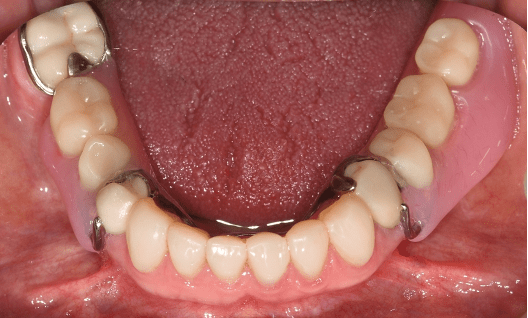

Metal dentures can be provided when there are a number of stable teeth to help support and hold the denture in place. It is often a healthier way to replace the teeth as it can minimise the coverage of the gums and movement that may harm the health of the remaining teeth. Selective crowns may be needed to optimise the support and retention.